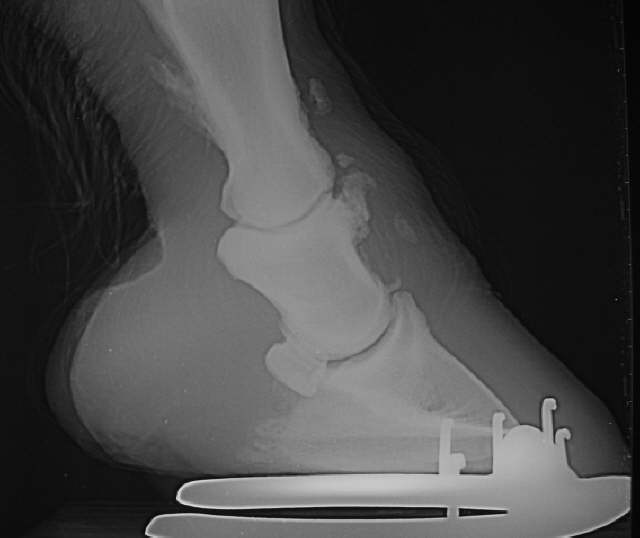

Sinker

Abgesunkenes Hufbein mit starken Veränerungen an den Anheftungsstellen der Gleichbeinbänder sowie Huf- und Krongelenksarthrose.